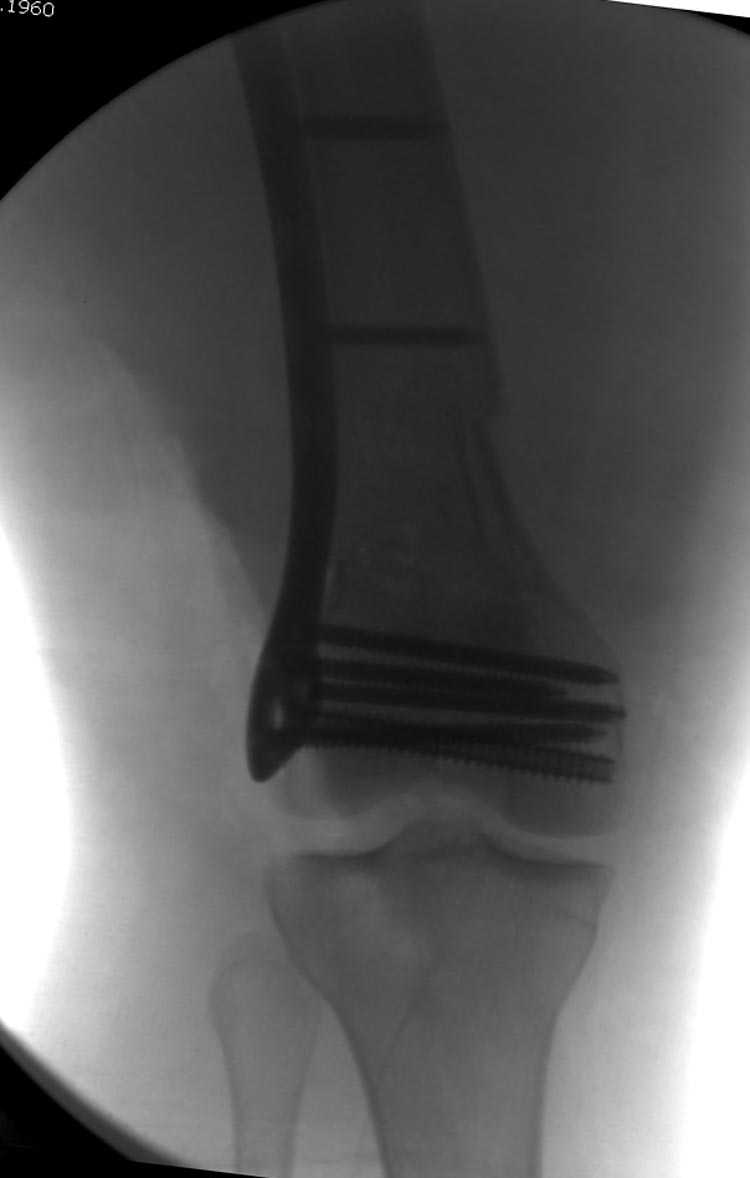

[Ortho] Дистальный перелом бедра

Почти все компании имеют пластины с угловой стабильностью, начиная от Stryker, Zimmer NCB и DePuy Polyaxial Plate . Если у NCB шуруп блокируется специальной шайбой, то Polyaxial Plate имеет вариабельный угол введения шурупов.

Поэтому такие меж и над- мыщелковые переломы более предпочтительным считается фиксировать мыщелковыми пластинами

Устанавливается из малого разреза "не вскрывая сустав" со стороны латерального мыщелка, и Insertion Jig позволяет установить пластину "мостовидно" перкутанно в проксимальном отделе, "не вскрывая и не трогая" место перелома.

Имя     : distal femur crm 2.jpg